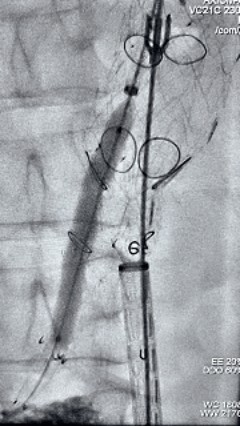

5. 撤出腹腔干导丝导管,经左肱动脉长鞘继续抓捕预置导丝将长鞘超选至另一侧内分支,后超选进肠系膜上动脉,沿导丝送入先健覆膜支架10*100mm一枚,近端重叠内分支,远端重叠于肠系膜上动脉,并予以10mm球囊后扩,手推造影显影良好。

8.gif

6. 解除束径,打开近端后释放,经肱动脉长鞘超选支架外分支,并进一步超选右侧肾动脉,交换加硬导丝,送入覆膜支架6*50mm和7*60mm各一枚,并予以球囊后扩张,手推造影显影良好。

11.gif    12.gif